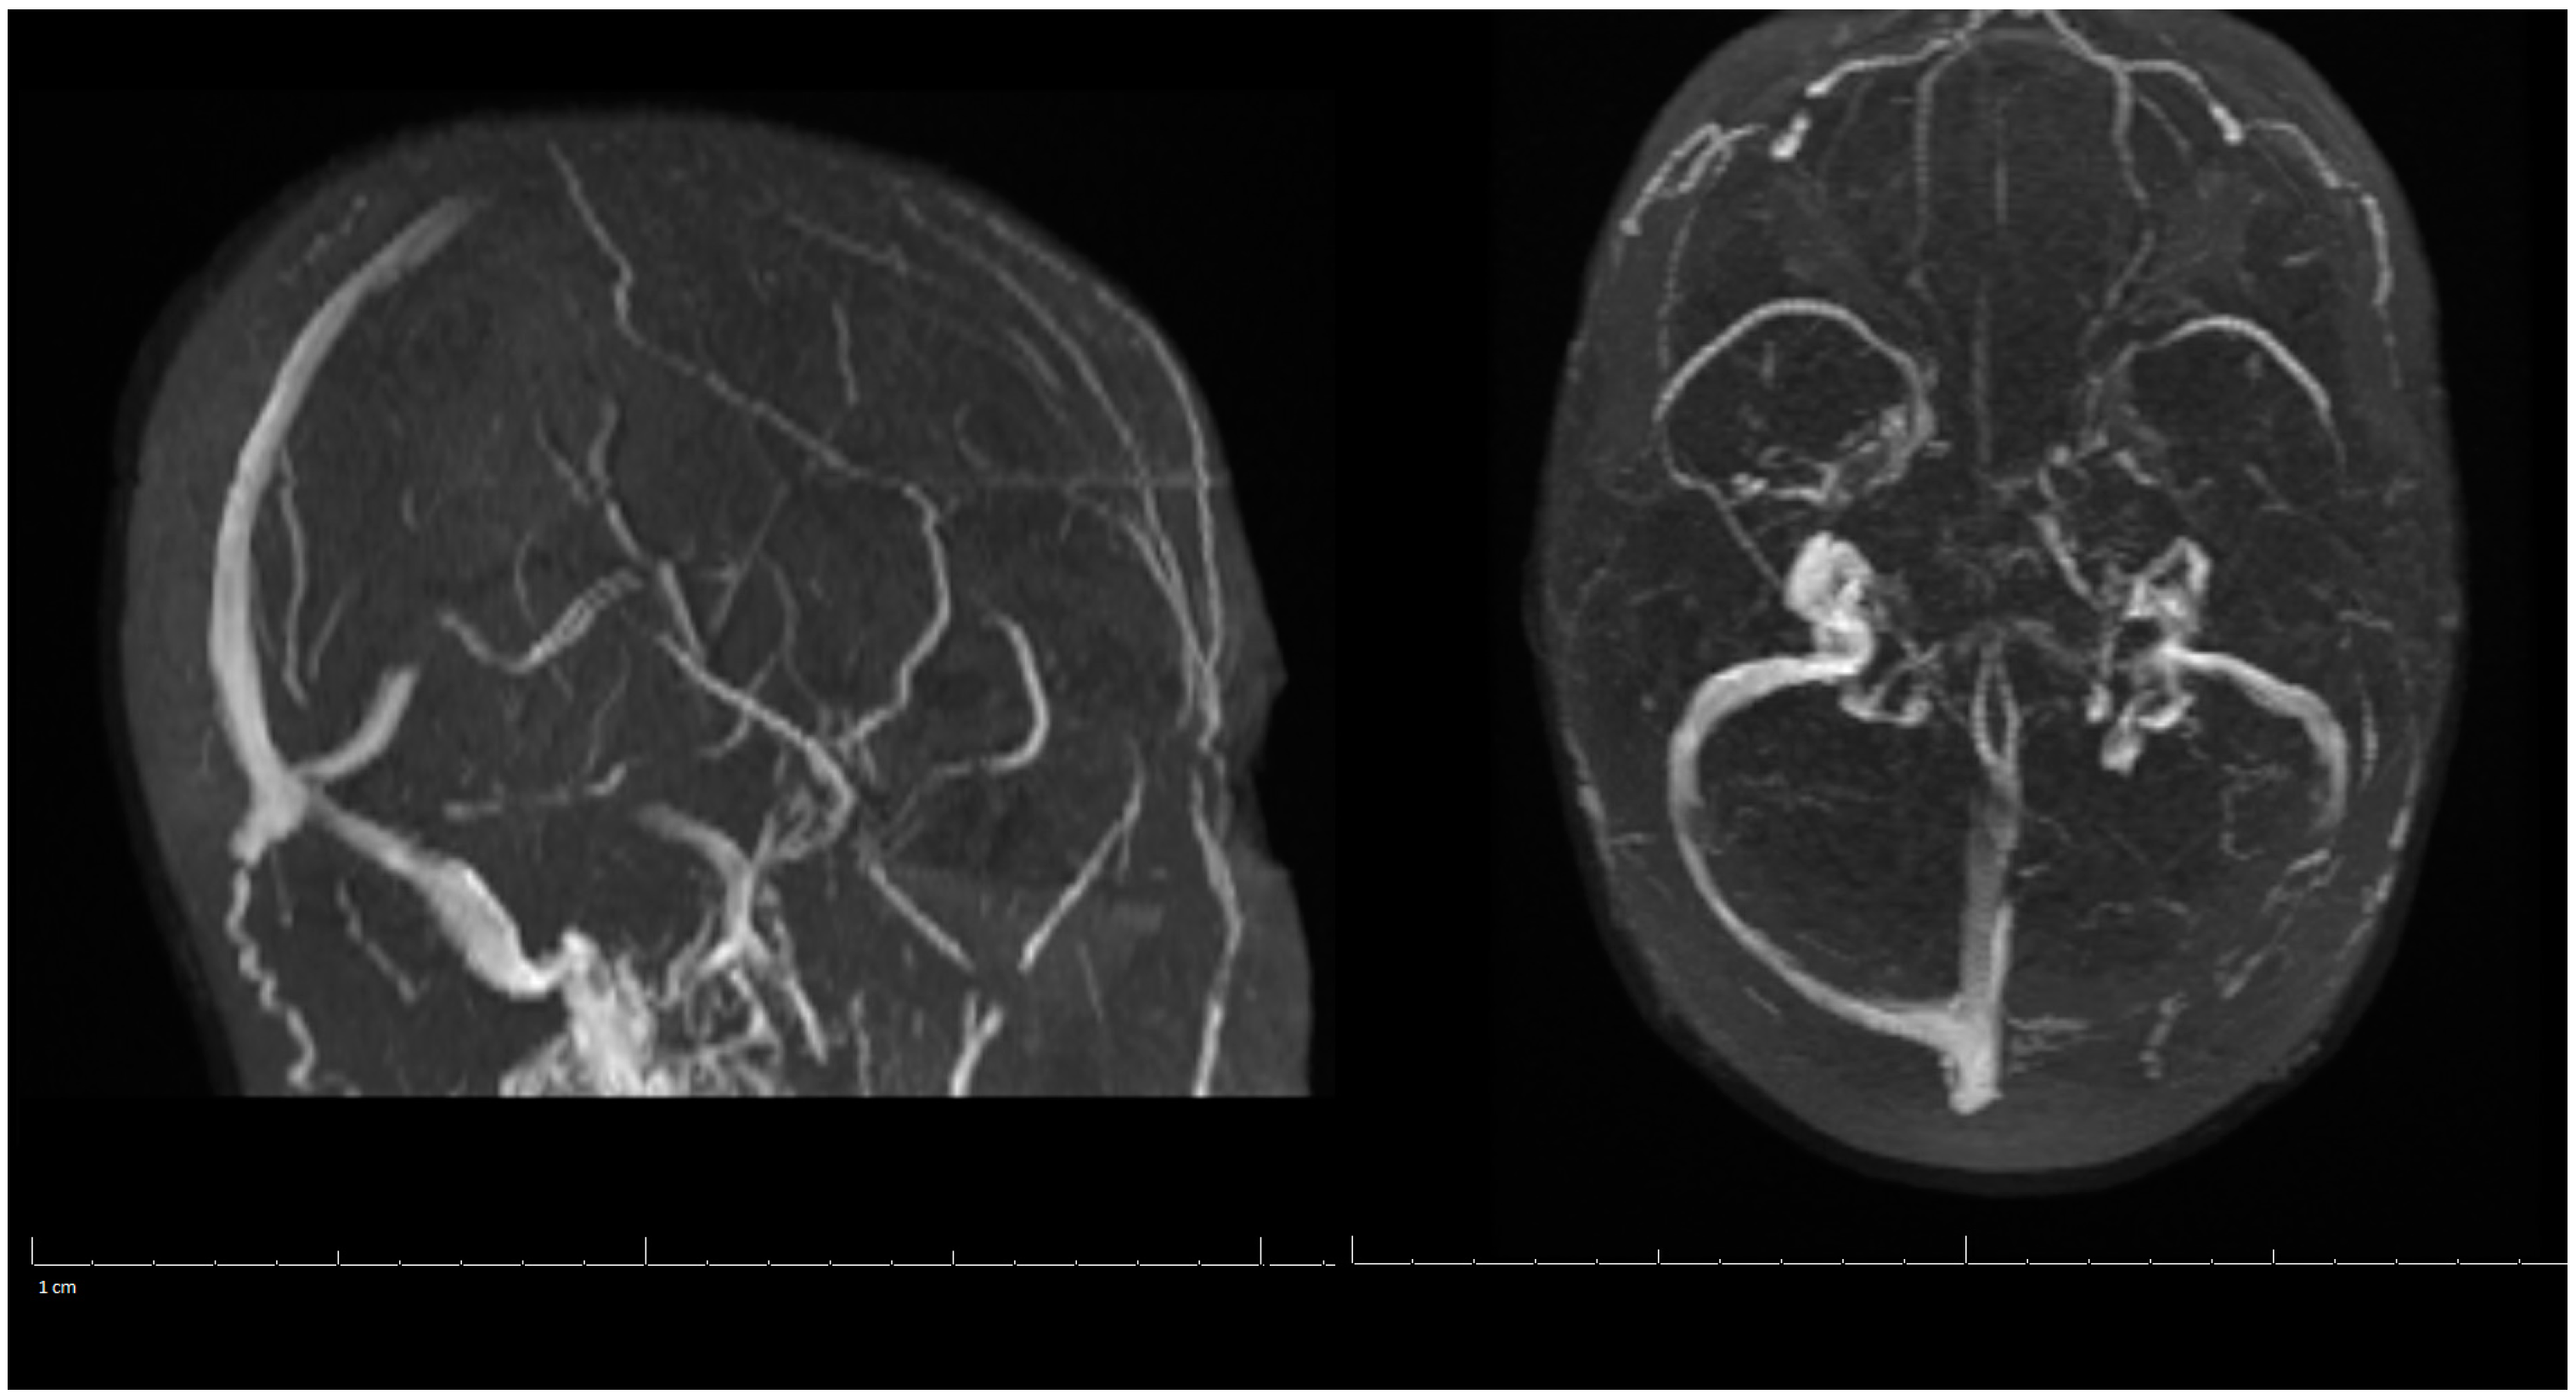

On her outpatient neurology clinic follow-up six weeks later, the patient was doing very well and largely back to her baseline. She still endorsed mild headaches about every other day and was using acetaminophen (Tylenol) for pain relief. The patient had been progressing well from attending regular physical therapy, occupational therapy, and speech therapy. Due to no seizure-like events, Keppra was to be weaned off to 500 mg every two weeks. Decreased Tylenol use was also suggested to avoid a rebound phenomenon. She was medically cleared to return to work and driving. Her three-month post-hospitalization MRV of the head showed stable left occipital intraparenchymal hemorrhage concerns for venous hemorrhage; partial thrombosis of the left transverse sinus improved in appearance compared with the previous examination three months ago; unremarkable appearance to the superior sagittal sinus, internal cerebral veins, inferior sagittal sinus, right transverse sinus, right and left sigmoid sinuses and internal jugular veins (Figure 3). A lipid panel showed improvement from inpatient levels. At the following telemedicine visit five months later, the patient reported only residual right hand weakness associated with reduced hand grip, but no further headaches. She discontinued Keppra at her last visit and has tolerated it well. Based on her most recent MRV, lipid panel, and clinical improvement, Xarelto and Lipitor were discontinued. The patient was advised to continue to follow a healthy diet and exercise to keep cholesterol under control, and avoid estrogen-containing birth control. There are no limitations on her activities from a neurological perspective. Another follow-up was scheduled in six months to ensure there are no new concerns, however, the patient did not show for this visit.

Figure 3.

MRV of the Head on 3-Months Post-Hospitalization.